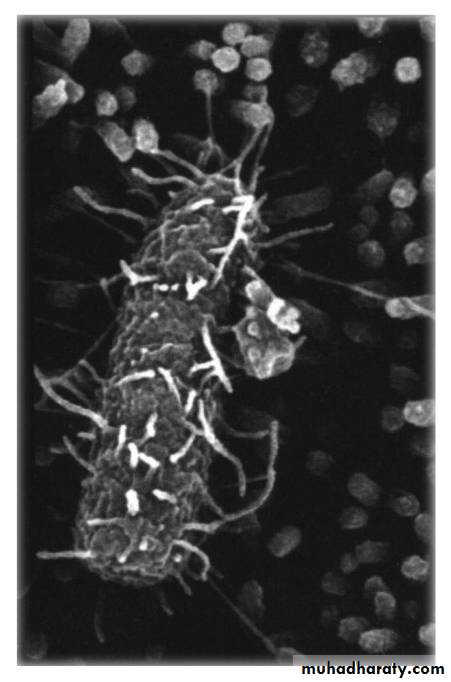

They have a characteristic swarming motility which is a wave like spreading of the MO across the entire surface of the agar.

P mirabilis, P. vulgaris, are easily recognized in LAB by the characteristic swarming phenomena on non selective culture media (SBA). Also produce distinct oder burnt chocolate.Both spp hydrolyze urea making the urine of patient with UTI with proteus more alkaline promoting kidney stone formation by precipitation of Mg and Ca. P mirabilis is differentiated from P. vulgaris by indole (mirabilis –ve, vulgaris +ve).

2- Culture:characteristic

sweet odor

On Nutrient and blood agar

a characteristic swarming